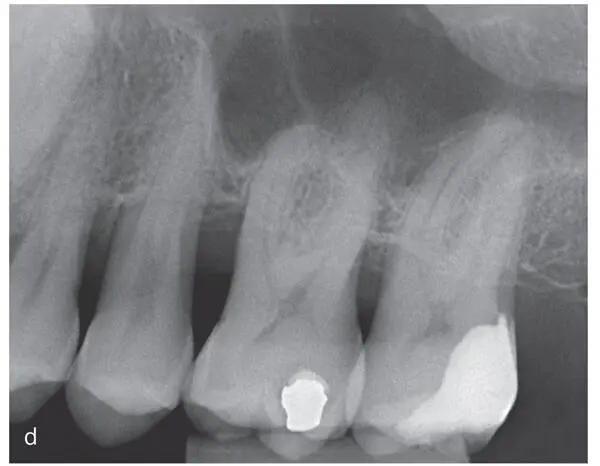

Figs 2-4a to fA 38-year-old (at time of admission) man with an inconspicuous general health and no medication. Diagnosis: periodontitis stage 4, grade C. This case continues in Fig 2-10. Baseline examinations: (a) first and fourth quadrants; (b) second and third quadrants; (c) frontal view; (d) maxillary arch; (e) mandibular arch; (f) baseline measurements of the clinical attachment level, including tooth migration and loosening, furcation involvement, and bleeding on probing (graphic illustration by Parostatus.de).

Figs 2-5a and bRadiographic examination of the patient introduced in Fig 2-3. (a) Panoramic radiograph and (b) intraoral radiographs. The radiographs show severe horizontal and vertical (locally) bone loss.